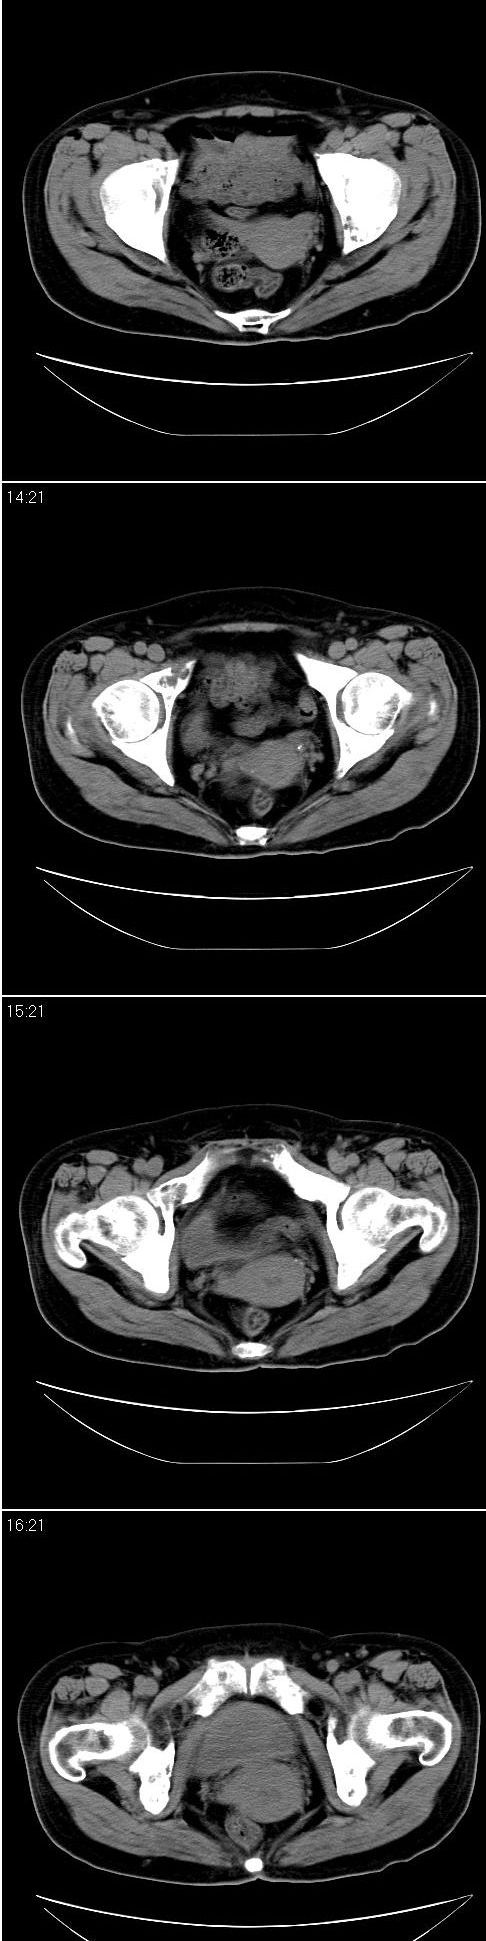

标题: CT13121:女,54岁。乳腺癌术后8年。 [打印本页]

女,54岁。乳腺癌术后8年。现感觉左腿酸困不适,并向下放散。左腿僵硬,不由自主。

典型溶骨型转移瘤。

骨盆及腰椎多发性溶骨性转移瘤.

成骨及融骨转移。

结合病史考虑乳腺癌术后多骨骨转移。

支持 骨转移瘤---混合型以溶骨为主

结合临床考虑多骨多灶性溶、成骨性转移。